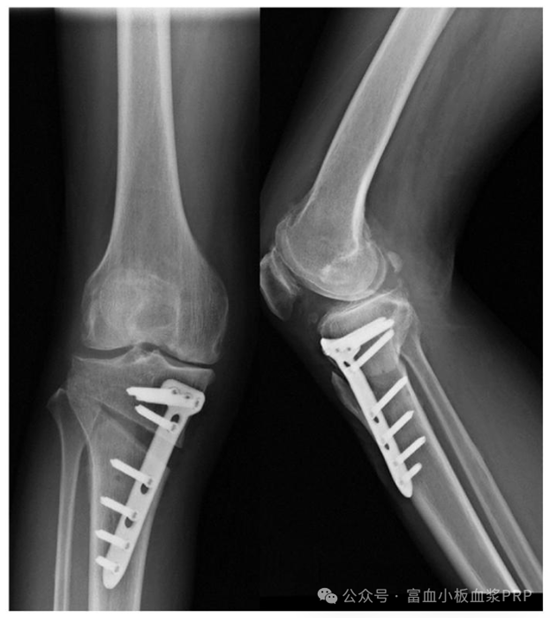

術前評估:醫(yī)生會通過 X 光、MRI 檢查膝蓋力線、軟骨磨損程度,再結合年齡、體重等,判斷是否適合手術;

手術 + PRP 注射:先做 HTO 手術(微創(chuàng),切口約 5 厘米),調整膝蓋力線;手術結束前,醫(yī)生會把提前制備好的 PRP 直接注射到關節(jié)腔和截骨部位,然后縫合傷口;